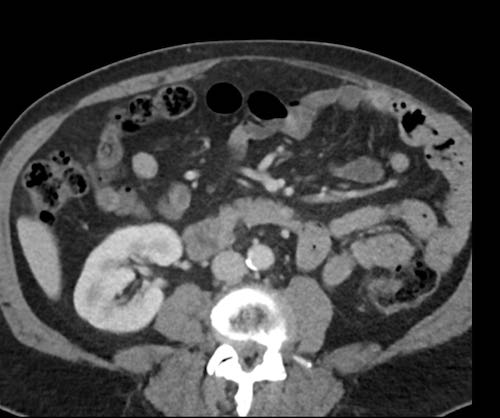

Ca lâm sàng 2

Cuộn qua các lát cắt.

Bạn có thể phát hiện tất cả các tổn thương cấy ghép phúc mạc không?